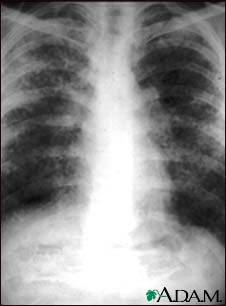

Sarcoid, stage II - chest X-ray

Sarcoid causes damage to the lung tissue that heals by scarring. The film shows a diffuse milky and granular appearance in the normally dark lung areas. This individual has marked decrease in lung function.